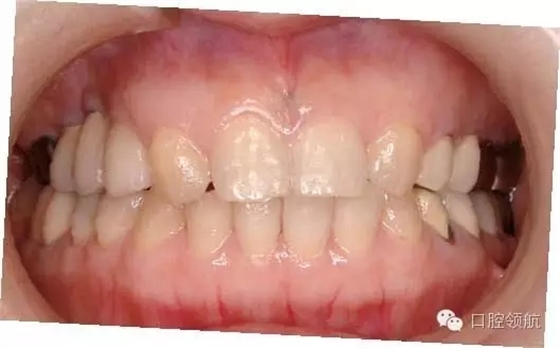

圖2 種植體埋入時的口內像

因骨板薄,為獲得初期穩(wěn)定性,種植體植入較淺,導致外部連接系統(tǒng)的愈合帽位于牙槽嵴頂上。

圖3 因為愈合帽位于牙槽嵴頂上,導致封閉創(chuàng)口的牙齦組織瓣不足,利用減張切開縫合。